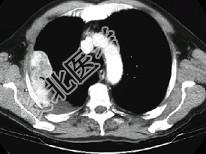

- 单项选择题男,53岁, 胸痛1月余加重2周,CT检查, 最可能的诊断为 ( )

A、右侧石棉肺胸膜斑

B、右侧良性胸膜间皮瘤

C、右侧恶性胸膜间皮瘤

D、右侧胸膜转移瘤

E、右侧胸膜弥漫增厚